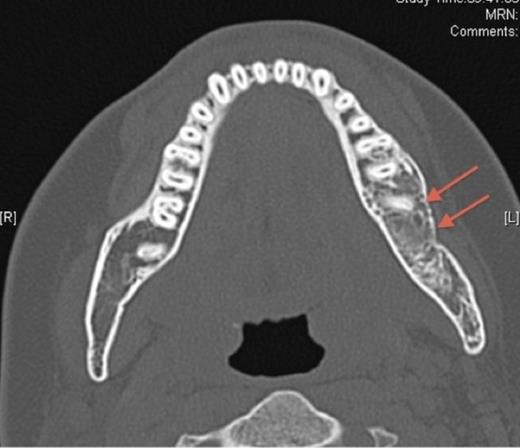

In October 2007, the patient represented with a swelling around the left angle of the mandible. Radiographs revealed no abnormalities but oral antibiotics were commenced with the clinical impression being that of osteomyelitis. Over the following month the swelling fluctuated in size, therefore a CT scan was undertaken. This showed a cystic enlargement at the left angle of the mandible with no cortical disruption or soft tissue involvement. With symptoms persisting the patient underwent exploration of the area under general anaesthesia and histopathology (which had previously been negative) now revealed desmoplastic fibroma.

Pre-operative axial CT showing the lesion in the left side of the mandible (denoted by arrows).